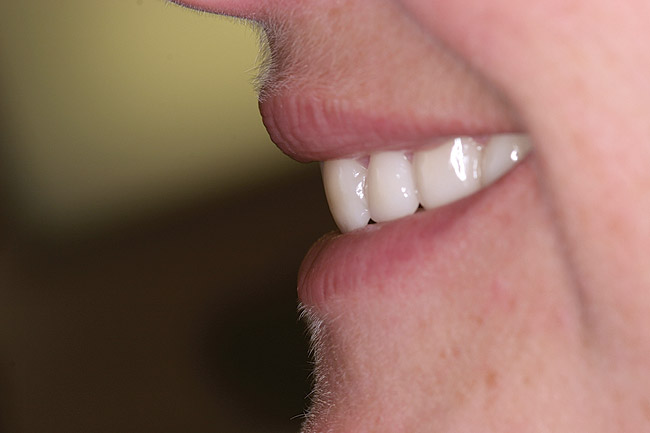

Figure 19 through Figure 21 The new restorations of the patient seen in Figure 18. The incisors now have a convex profile and lingualized incisal edge. Lip and phonetic comfort were normalized.

Figure 19

Figure 20

Figure 21

The patient seen in Figure 18 was unable to get comfortable with the restored incisal edge position. The re-treated position seen in Figure 19 through Figure 21 was a subtle, yet profound, change. Because of her thin lip structure (highly muscular), even a small error was detectable and interfered with her lip function.